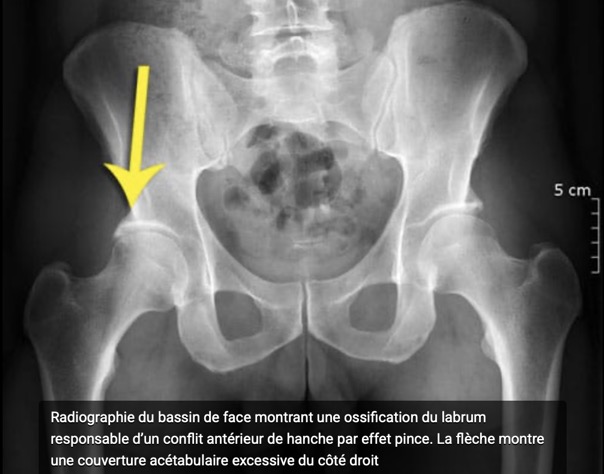

- 2. Le conflit de type PINCER (b) : bord de l'acétabulum trop proéminent ou cotyle trop profond